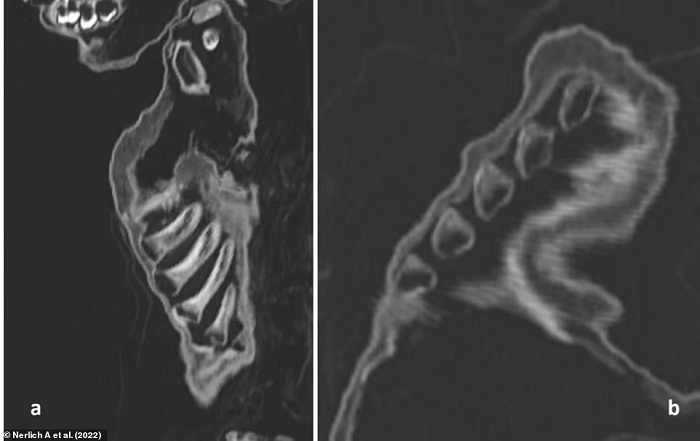

Tuy nhiên, kết quả chụp CT thể hiện xương sườn của cậu bị biến dạng, dấu hiệu của căn bệnh chuyển hóa xương (Metabolic Bone Disease - MBD) thường được thấy trong các trường hợp mắc bệnh còi xương nghiêm trọng. Hình ảnh chụp cắt lớp cũng cho thấy tình trạng đặc trưng của bệnh viêm phổi.

Đối với các nhà nghiên cứu, điều này cho thấy rằng mặc dù đứa trẻ mới biết đi đã được cho ăn đủ để tăng cân nhưng vẫn bị suy dinh dưỡng, hậu quả của việc bị giữ trong nhà không cho tiếp xúc với ánh nắng mặt trời khiến cơ thể cậu bé bị thiếu vitamin D.

Với những bằng chứng thu thập được, nhóm nghiên cứu kết luận rằng, cậu bé đã chết vì bệnh viêm phổi cũng như cơ thể thiếu hụt những nguồn dinh dưỡng cần thiết.